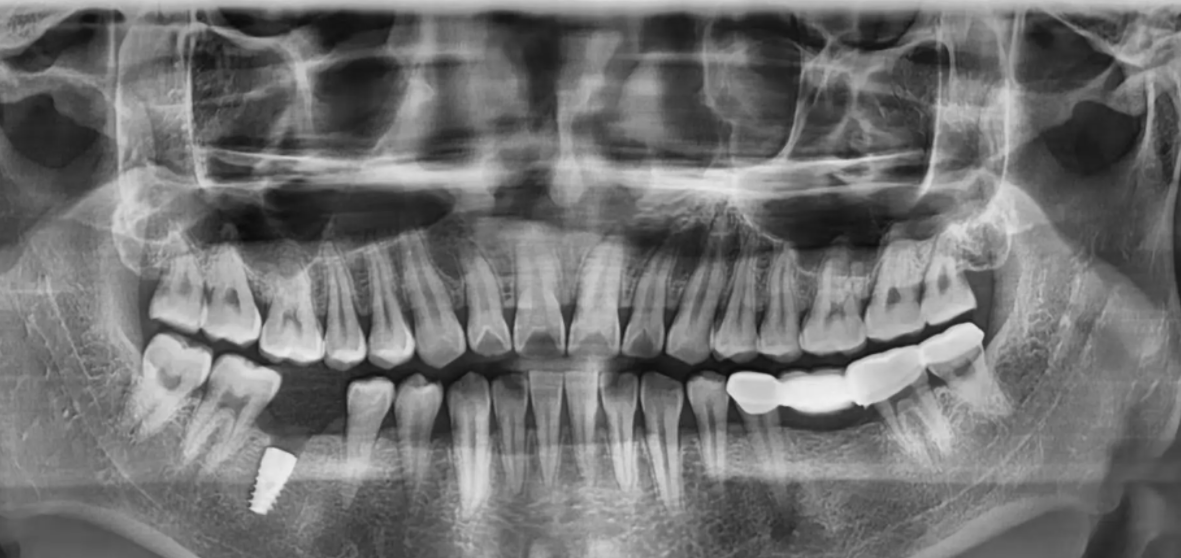

1、術(shù)前準(zhǔn)備,進(jìn)行種牙前,必要的X片、CT片以及抽血化驗(yàn)、量血壓等都是需要體檢檢查的。檢查完成后,醫(yī)生根據(jù)每個人的情況進(jìn)行個性化種植方案設(shè)計(jì)。